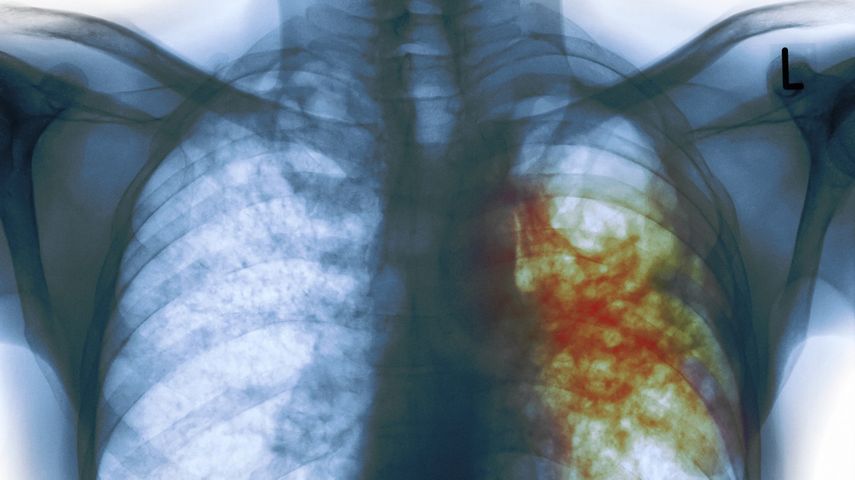

Hay más de 10 millones de personas con tuberculosis en el mundo, alertó la OMS

Según la OMS, el año pasado 10,4 millones de personas sufrían esta enfermedad, que causó 1,8 millones de muertes en 2016.